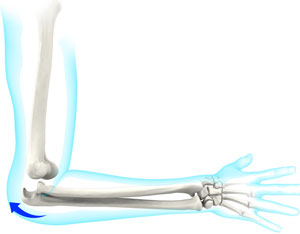

Elbow Contracture

Elbow contracture refers to a stiff elbow with a limited range of motion. It is a common complication following elbow...